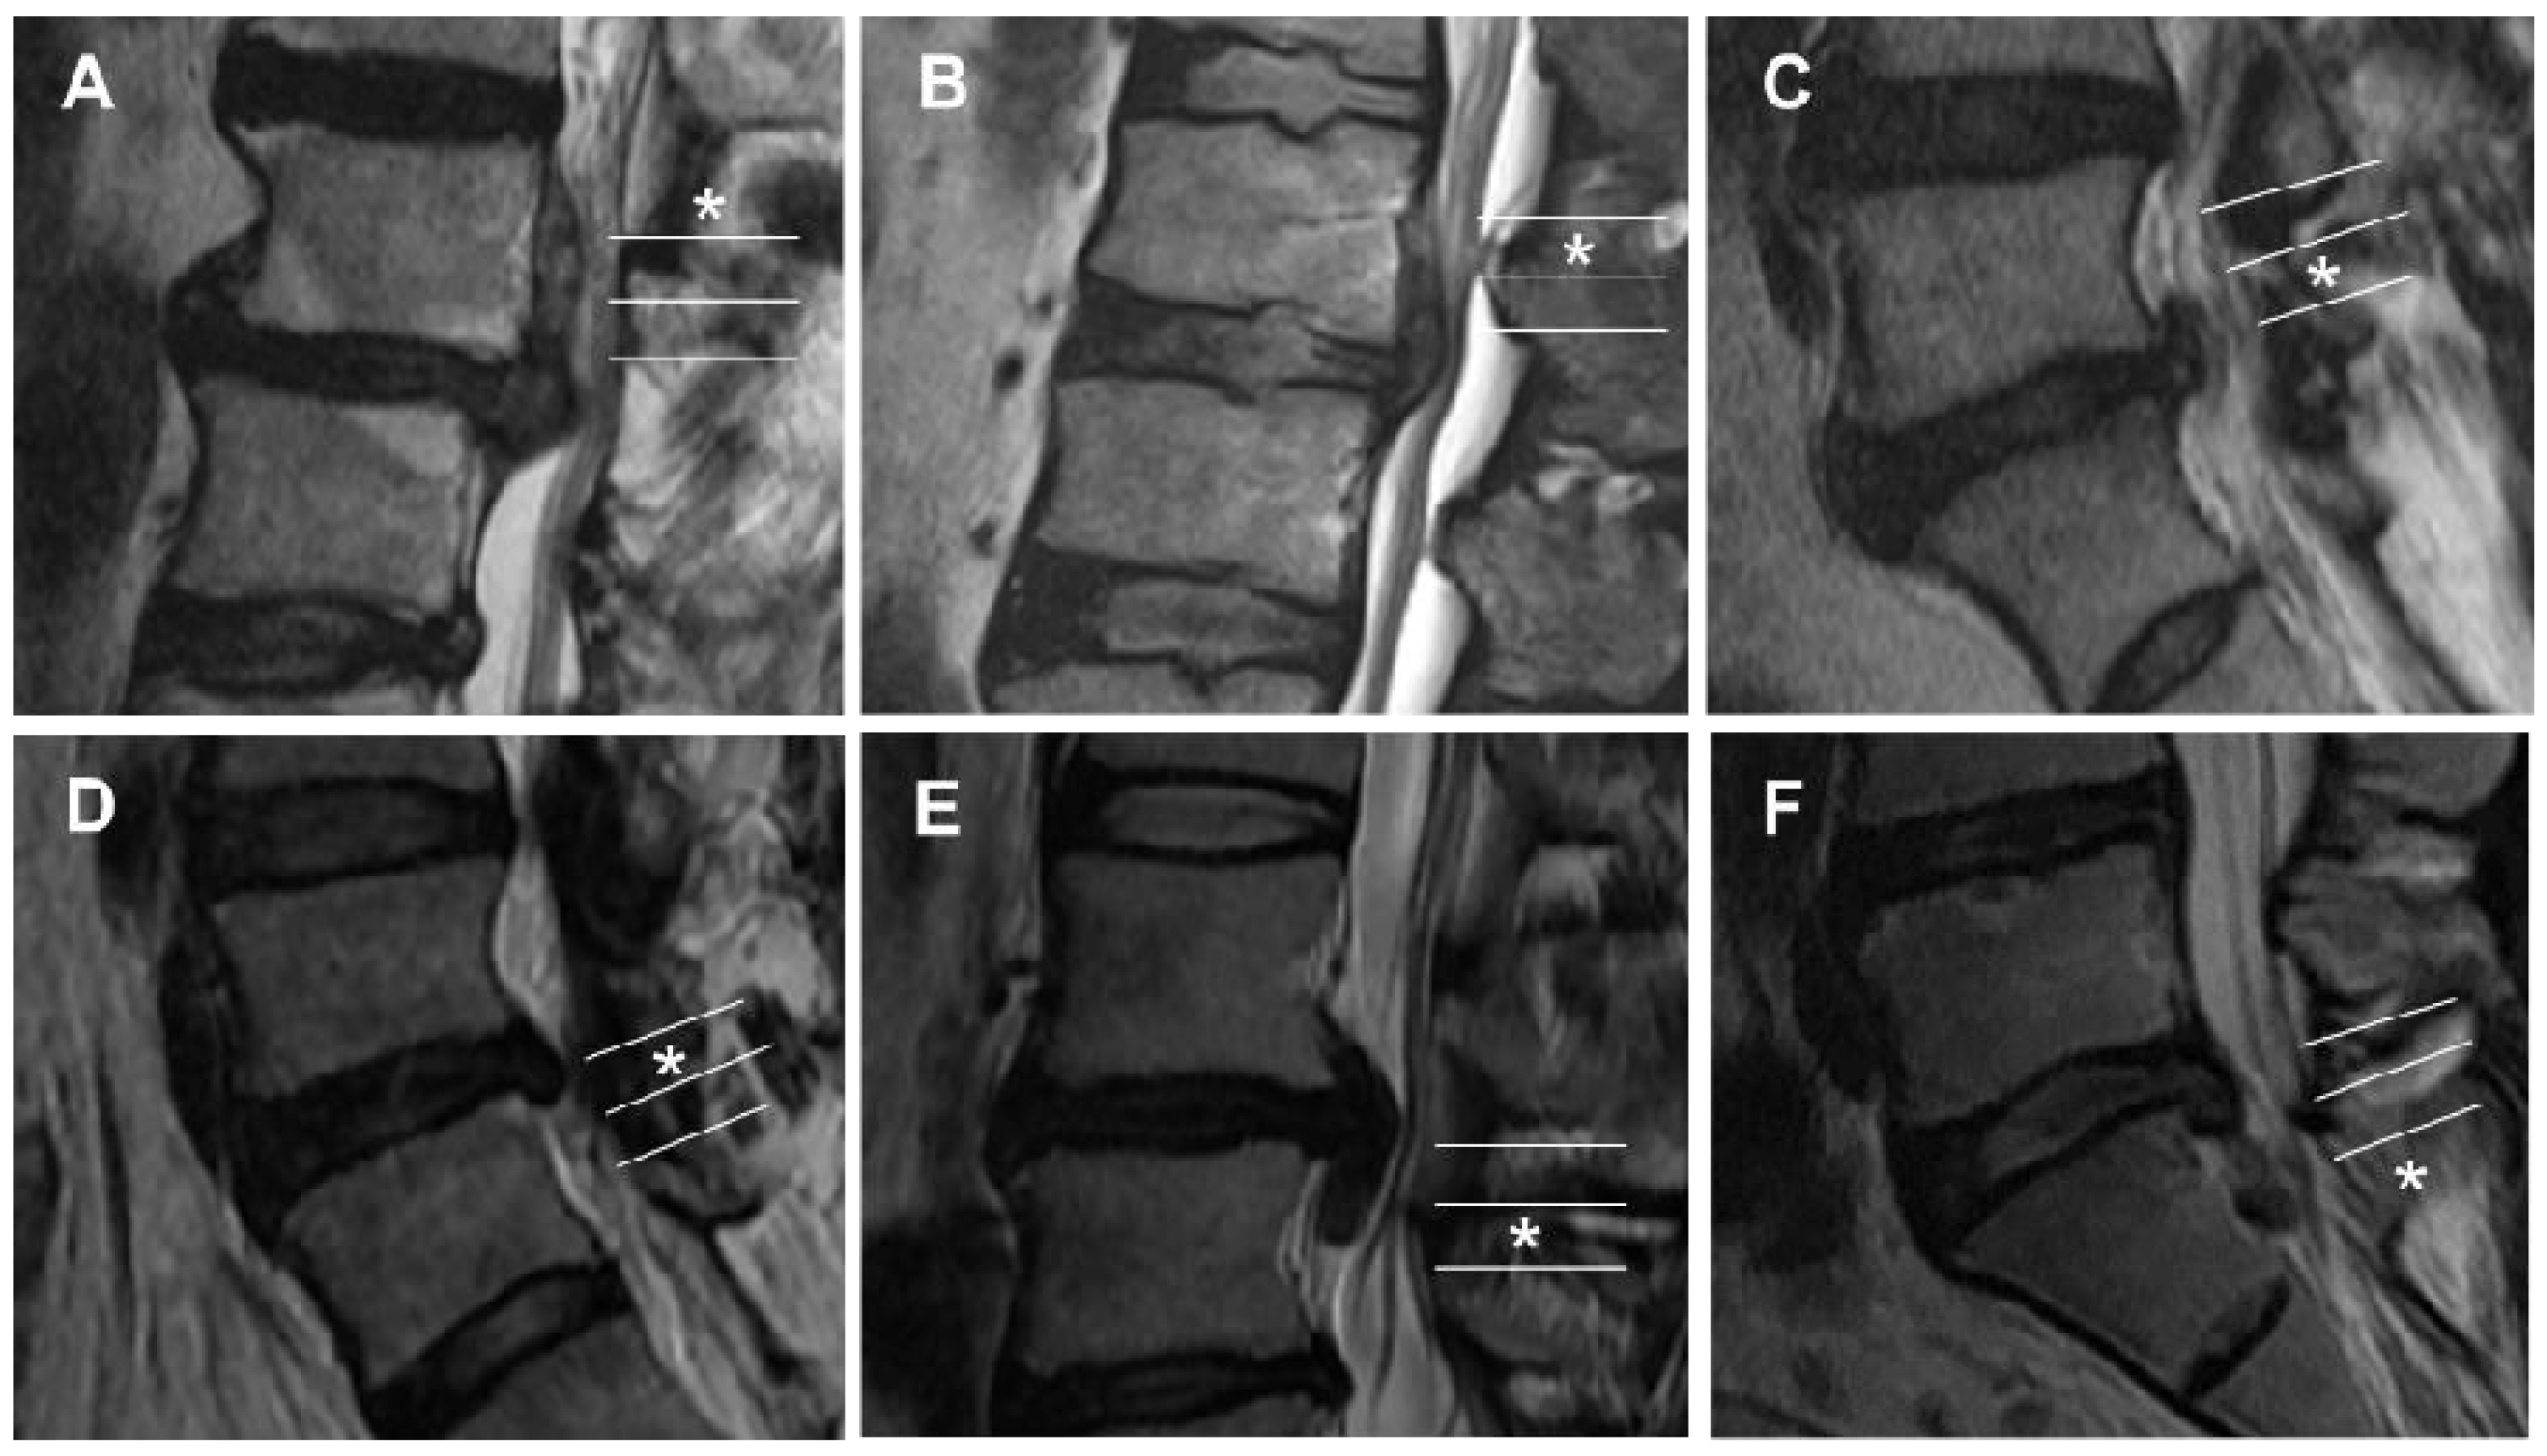

| Grade | Direction and Degree | Range of Migration Distance |

|---|---|---|

| 1 | Superior very high | Beyond the inferior margin of the upper pedicle |

| 2 | Superior high | From the inferior margin of the upper pedicle to the midpoint between the inferior margin of the upper pedicle and superior disc margin |

| 3 | Superior low | From the midpoint between the inferior margin of the upper pedicle and superior disc margin to the superior disc margin |

| 4 | Inferior low | From the inferior disc margin to the midpoint between the inferior margin of the lower pedicle and inferior disc margin |

| 5 | Inferior high | From the midpoint between the inferior margin of the lower pedicle and inferior disc margin to the inferior margin of the lower pedicle |

| 6 | Inferior very high | Beyond the inferior margin of the lower pedicle |